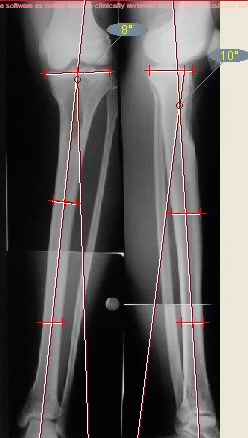

Продолжение обсуждения, начатого в октябре прошлого года (см. здесь) Наконец-то оперировали эту пациентку. Биопсию сделали - опухолевого ничего нет. Пока все участвовавшие в обследовании смежные специалисты и ортопеды сошлись, что это молокальная монооссальная фиброзная дисплазия. 20 марта наложили аппарат, сделали чрескожную остеотомию. К 3 апреля все докрутили. Сегодня заштифтовали. Начальные и итоговые снимки в приложении. Рекурвацию можно было еще немного больше устранить, и чуть кзади сместить диафиз. Но вроде и так ничего выглядит, по сравнению с тем, что было. Комментарии приветствуются.

ничего не понимаю в детской и ортопедии, но в боковой проекции нет рекурвации,

а даже немного гиперкоррекция, что по-моему есть хорошо. Кортикалы по задней стенке совпадают, диафиз на одну неправду кзади.

Есть клиновидный диастаз, контакт основных отломков на очень небольшой площади только в задненаружном отделе. Так что там скорее межотломковая дистракция, а не компрессия.